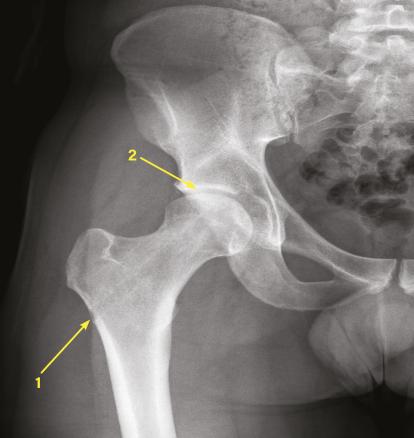

La radiographie conventionnelle n’est pas indiquée pour le diagnostic d’ostéonécrose. L’IRM est, à l’heure actuelle, l’examen de référence. Elle doit donc être proposée devant toute douleur de hanche du sujet jeune non expliquée par une radiographie. Associée à la radiographie (face et profil de Dunn), elle permet également d’éliminer les diagnostics différentiels les plus fréquents (conflit acétabulaire, atteinte du labrum, kyste arthrosynovial, ostéochondrite…).